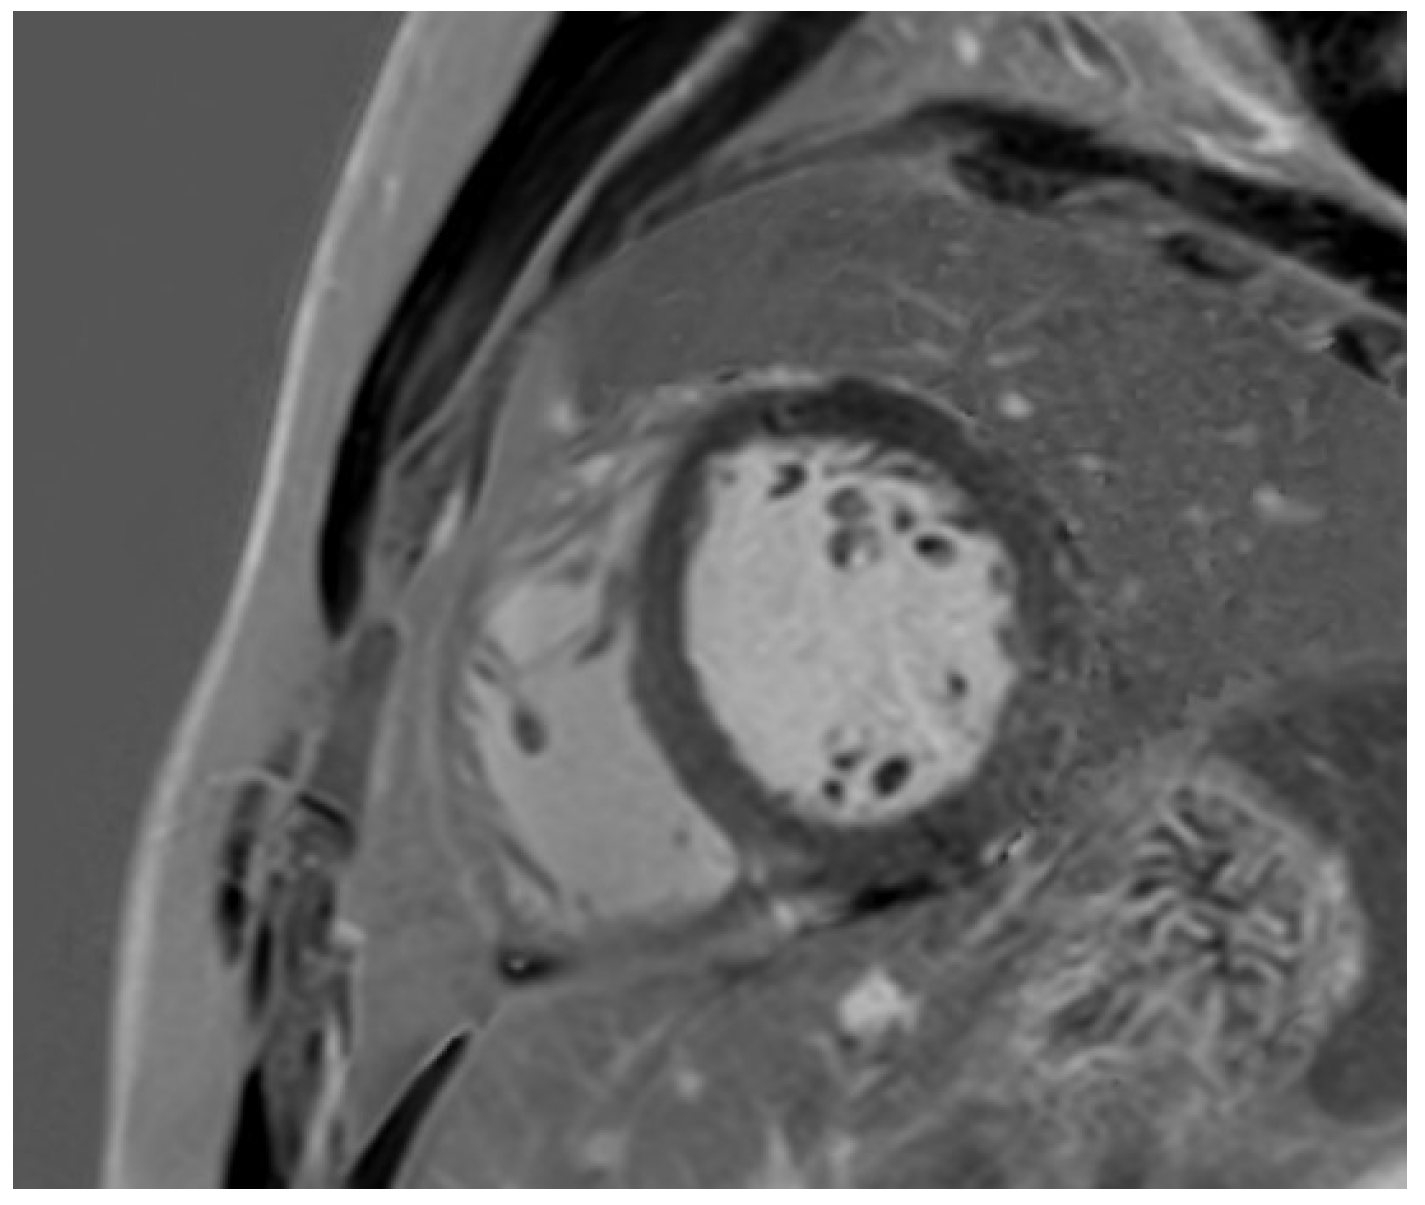

11. Left Ventricular Hypertrabeculation